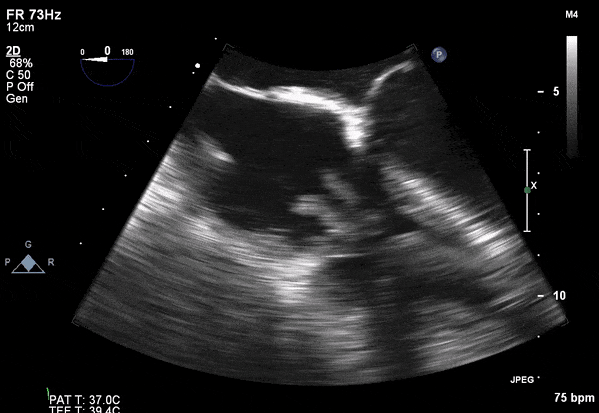

Role of Echocardiography

- Echo plays an important role in the diagnosis of infective endocarditis.

- Helps identify vegetations, new valvular lesions, abscess, and other complications of endocarditis.

- Transthoracic (TTE) should be performed in all cases of suspected infective endocarditis

- Transesophageal (TEE) should be performed if TTE images are inadequate or ongoing suspicion for infective endocarditis.

Transesophageal Images